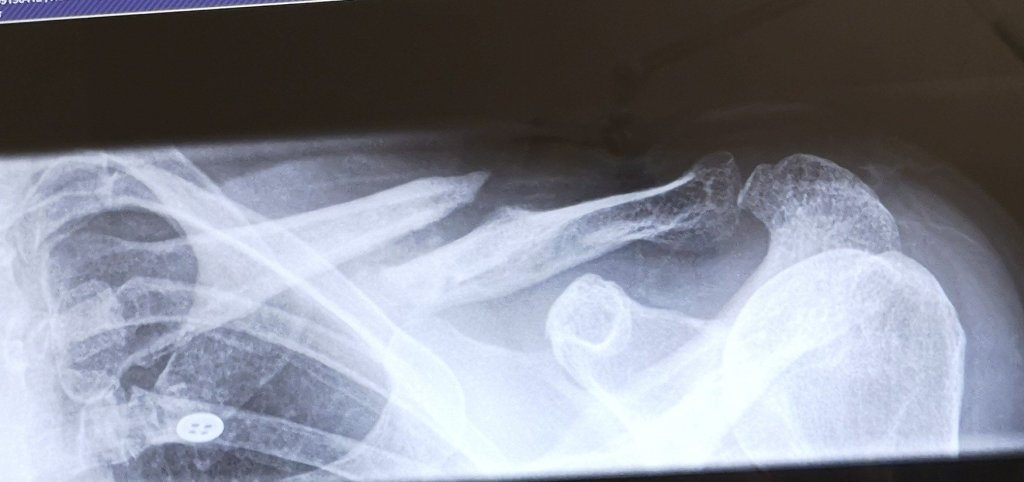

It’s great that Tom will be able to help as I am still unable to lift anything heavy, in fact lift anything at all, as after 14 weeks, my clavicle bones are still practising a strict social-distancing policy, and are showing no signs of even starting to heal, so I will be limited to walking and just encouraging the boys on with the tasks that need to be done, providing food and drink when needed….